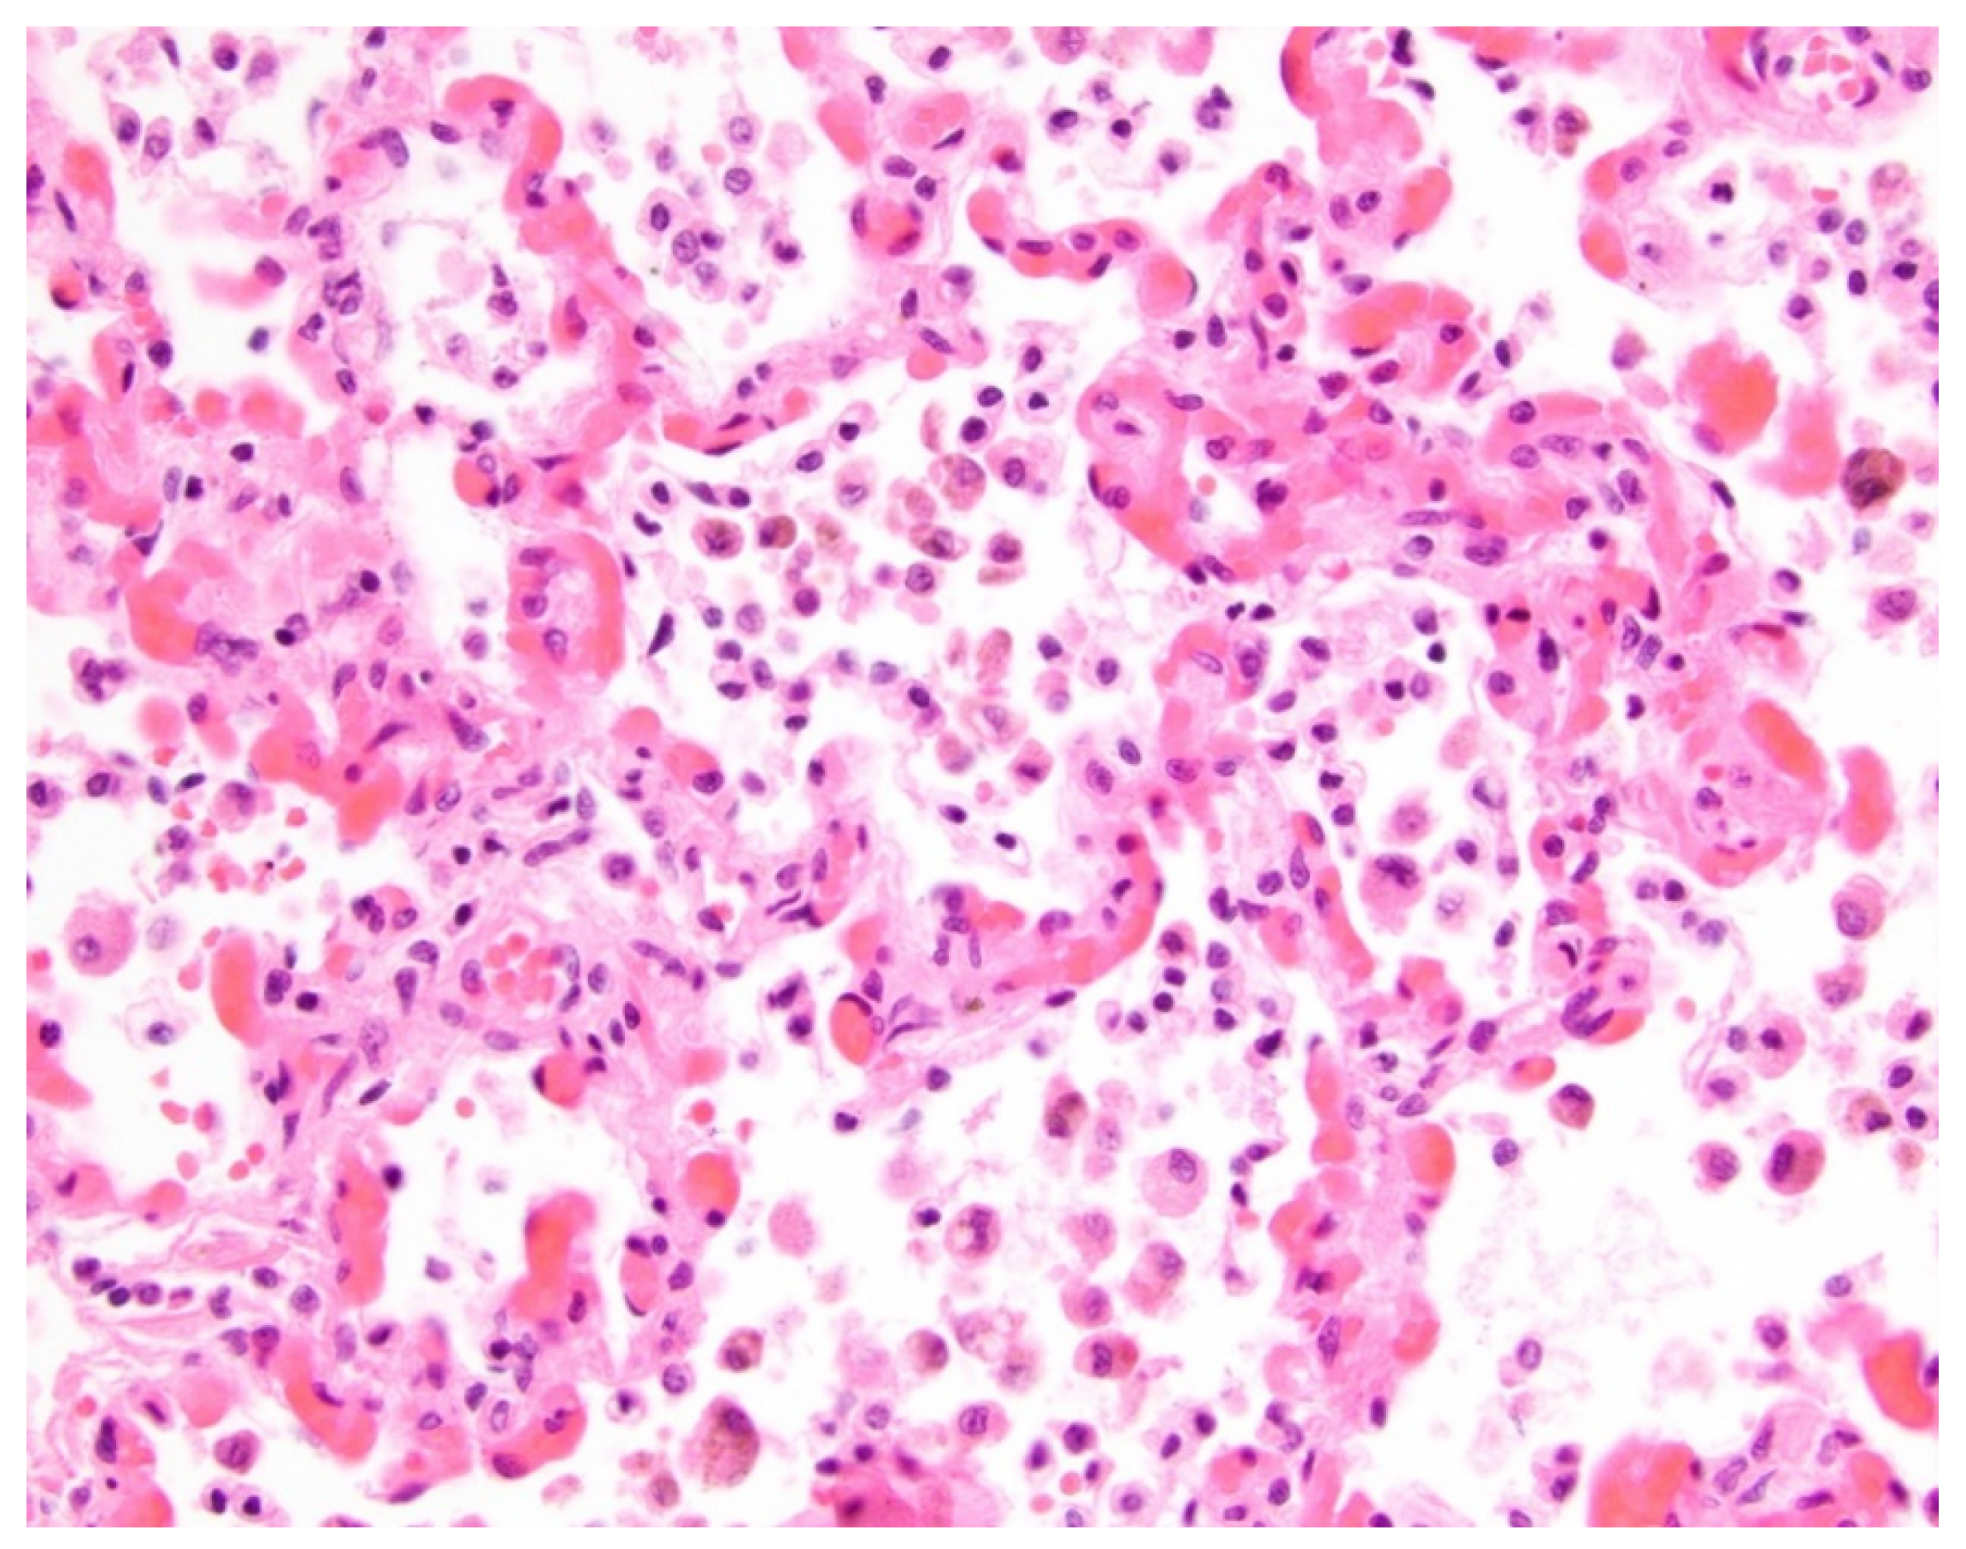

Figure 2. Histologic findings of aspiration in a 10-month-old female with pulmonary vein stenosis. At autopsy, the lungs showed features of pulmonary vein stenosis, and there also was an acute exudative and necrotizing pneumonia. What is pictured is acute exudative pneumonia, with airspaces filled by fibrin, neutrophils, and cellular debris (hematoxylin and eosin stain; original magnification, 400×).

In Group 1 (PVS and aspiration), among 19 thoracic MDCT studies, three lung abnormalities were observed, including GGO in 17 thoracic MDCT studies (89.5%), consolidation in 16 thoracic MDCT studies (84.5%), and septal thickening in 16 thoracic MDCT studies (84.5%) (Figure 1 and Figure 2).

We believe that the presence of consolidation, which was the only significantly different pleuropulmonary abnormality on thoracic MDCT in pediatric patients with PVS and aspiration, can be explained by underlying pathophysiology. Aspirated food materials, saliva, and/or oropharyngeal flora introduced into the airways descends through the bronchial tree into lung parenchyma, producing a chemical pneumonitis and/or bacterial pneumonia [28,29,30]. On imaging, such as thoracic MDCT, the resulting acute exudative pneumonia manifests as airspace disease (e.g., consolidation), reflecting the presence of underlying erythrocytes, neutrophils, desquamated epithelial cells, fibrin, and fluid within the alveoli [31,32]. Therefore, the presence of consolidation on thoracic MDCT studies in pediatric patients with PVS should raise suspicion for concomitant aspiration, which has been shown to be associated with poor outcomes in pediatric patients with PVS. However, this is a potentially modifiable risk factor [17]. A recently published study speculated that lung and pleural changes associated with aspiration may directly impact the cells that comprise pulmonary veins’ endothelium, resulting in hyper-proliferation and intraluminal obliteration [17].